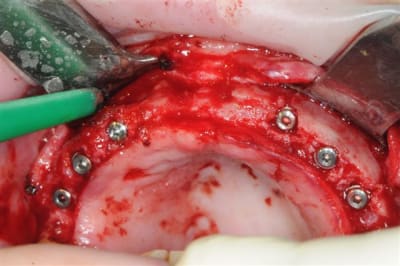

je peux enfin confirmer que la greffe biobank, autorise l'expansion en deuxième intention.

même si je n'ai pas fait un super bombé vestibulaire je me suis permis de faire un mini expansion de crête en particulier sur 22

os magnifiquement vascularisé! excellente adhérence du greffon.

Concernant la résorption du greffon, même constatations que Growler: aucune, les seuls zones qui ont fait reculer la date d'intervention, de 2 mois sont des zones de jonction avec l'os du patient qui avait du mal à fusionner car trop fin au départ (moins d'un mm)je pense.

Faisons un peu de prospective, je joins la photo 3D réalisé y a plusieur mois montrant ce qui est espéré et la photo que tu à mis en ligne sur eugenol, chacun sera en mesure de jugé de la qualité du résultat obtenu.